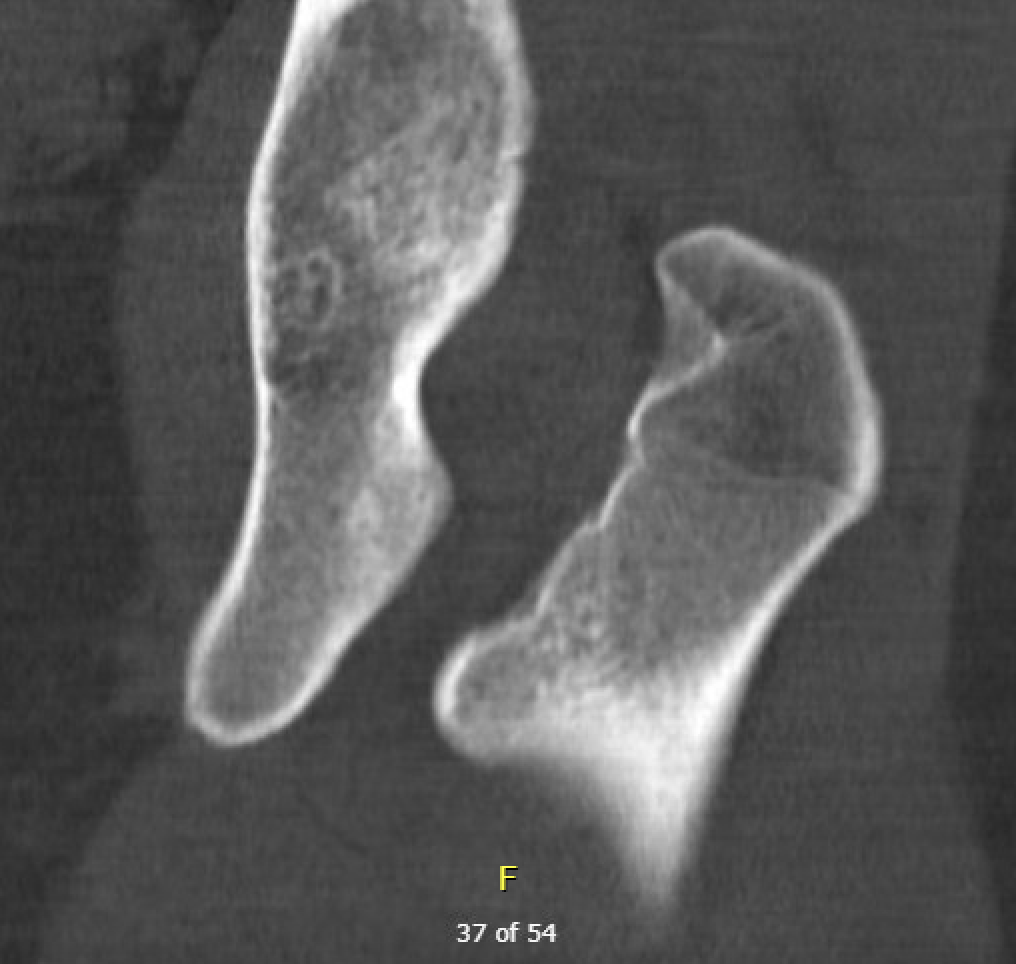

CT

IFI

IFIIFIIFI